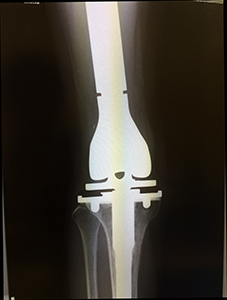

患肢温存のため、確実な腫瘍切除の後失われた組織をいかに再建するかが重要な課題になります。この目的のために、状況に応じ人工関節置換、神経・血管・骨表面に対する術中アルコール処理法、皮膚筋弁移植・遊離骨移植(腫瘍切除で皮膚に大きな欠損が生じた場合、背中やお腹、大腿部の皮膚・筋肉を血管と共に採取し欠損部を覆います;形成外科と連携)などを準備しています。

骨肉腫症例 人工関節置換術